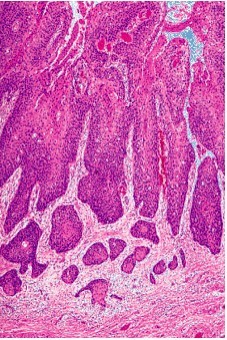

Vulvar squamous cell carcinoma: tumors exophytic or ulcertive (can invade neighboring structures- vagina, rectum). Can spread to inguinal, femoral, pelvic lymph nodes.

See keratin pearl formation

*Verrucous carcinoma= caused by HPV 6 or 11; well-differentiated, grows slowly, better prognosis